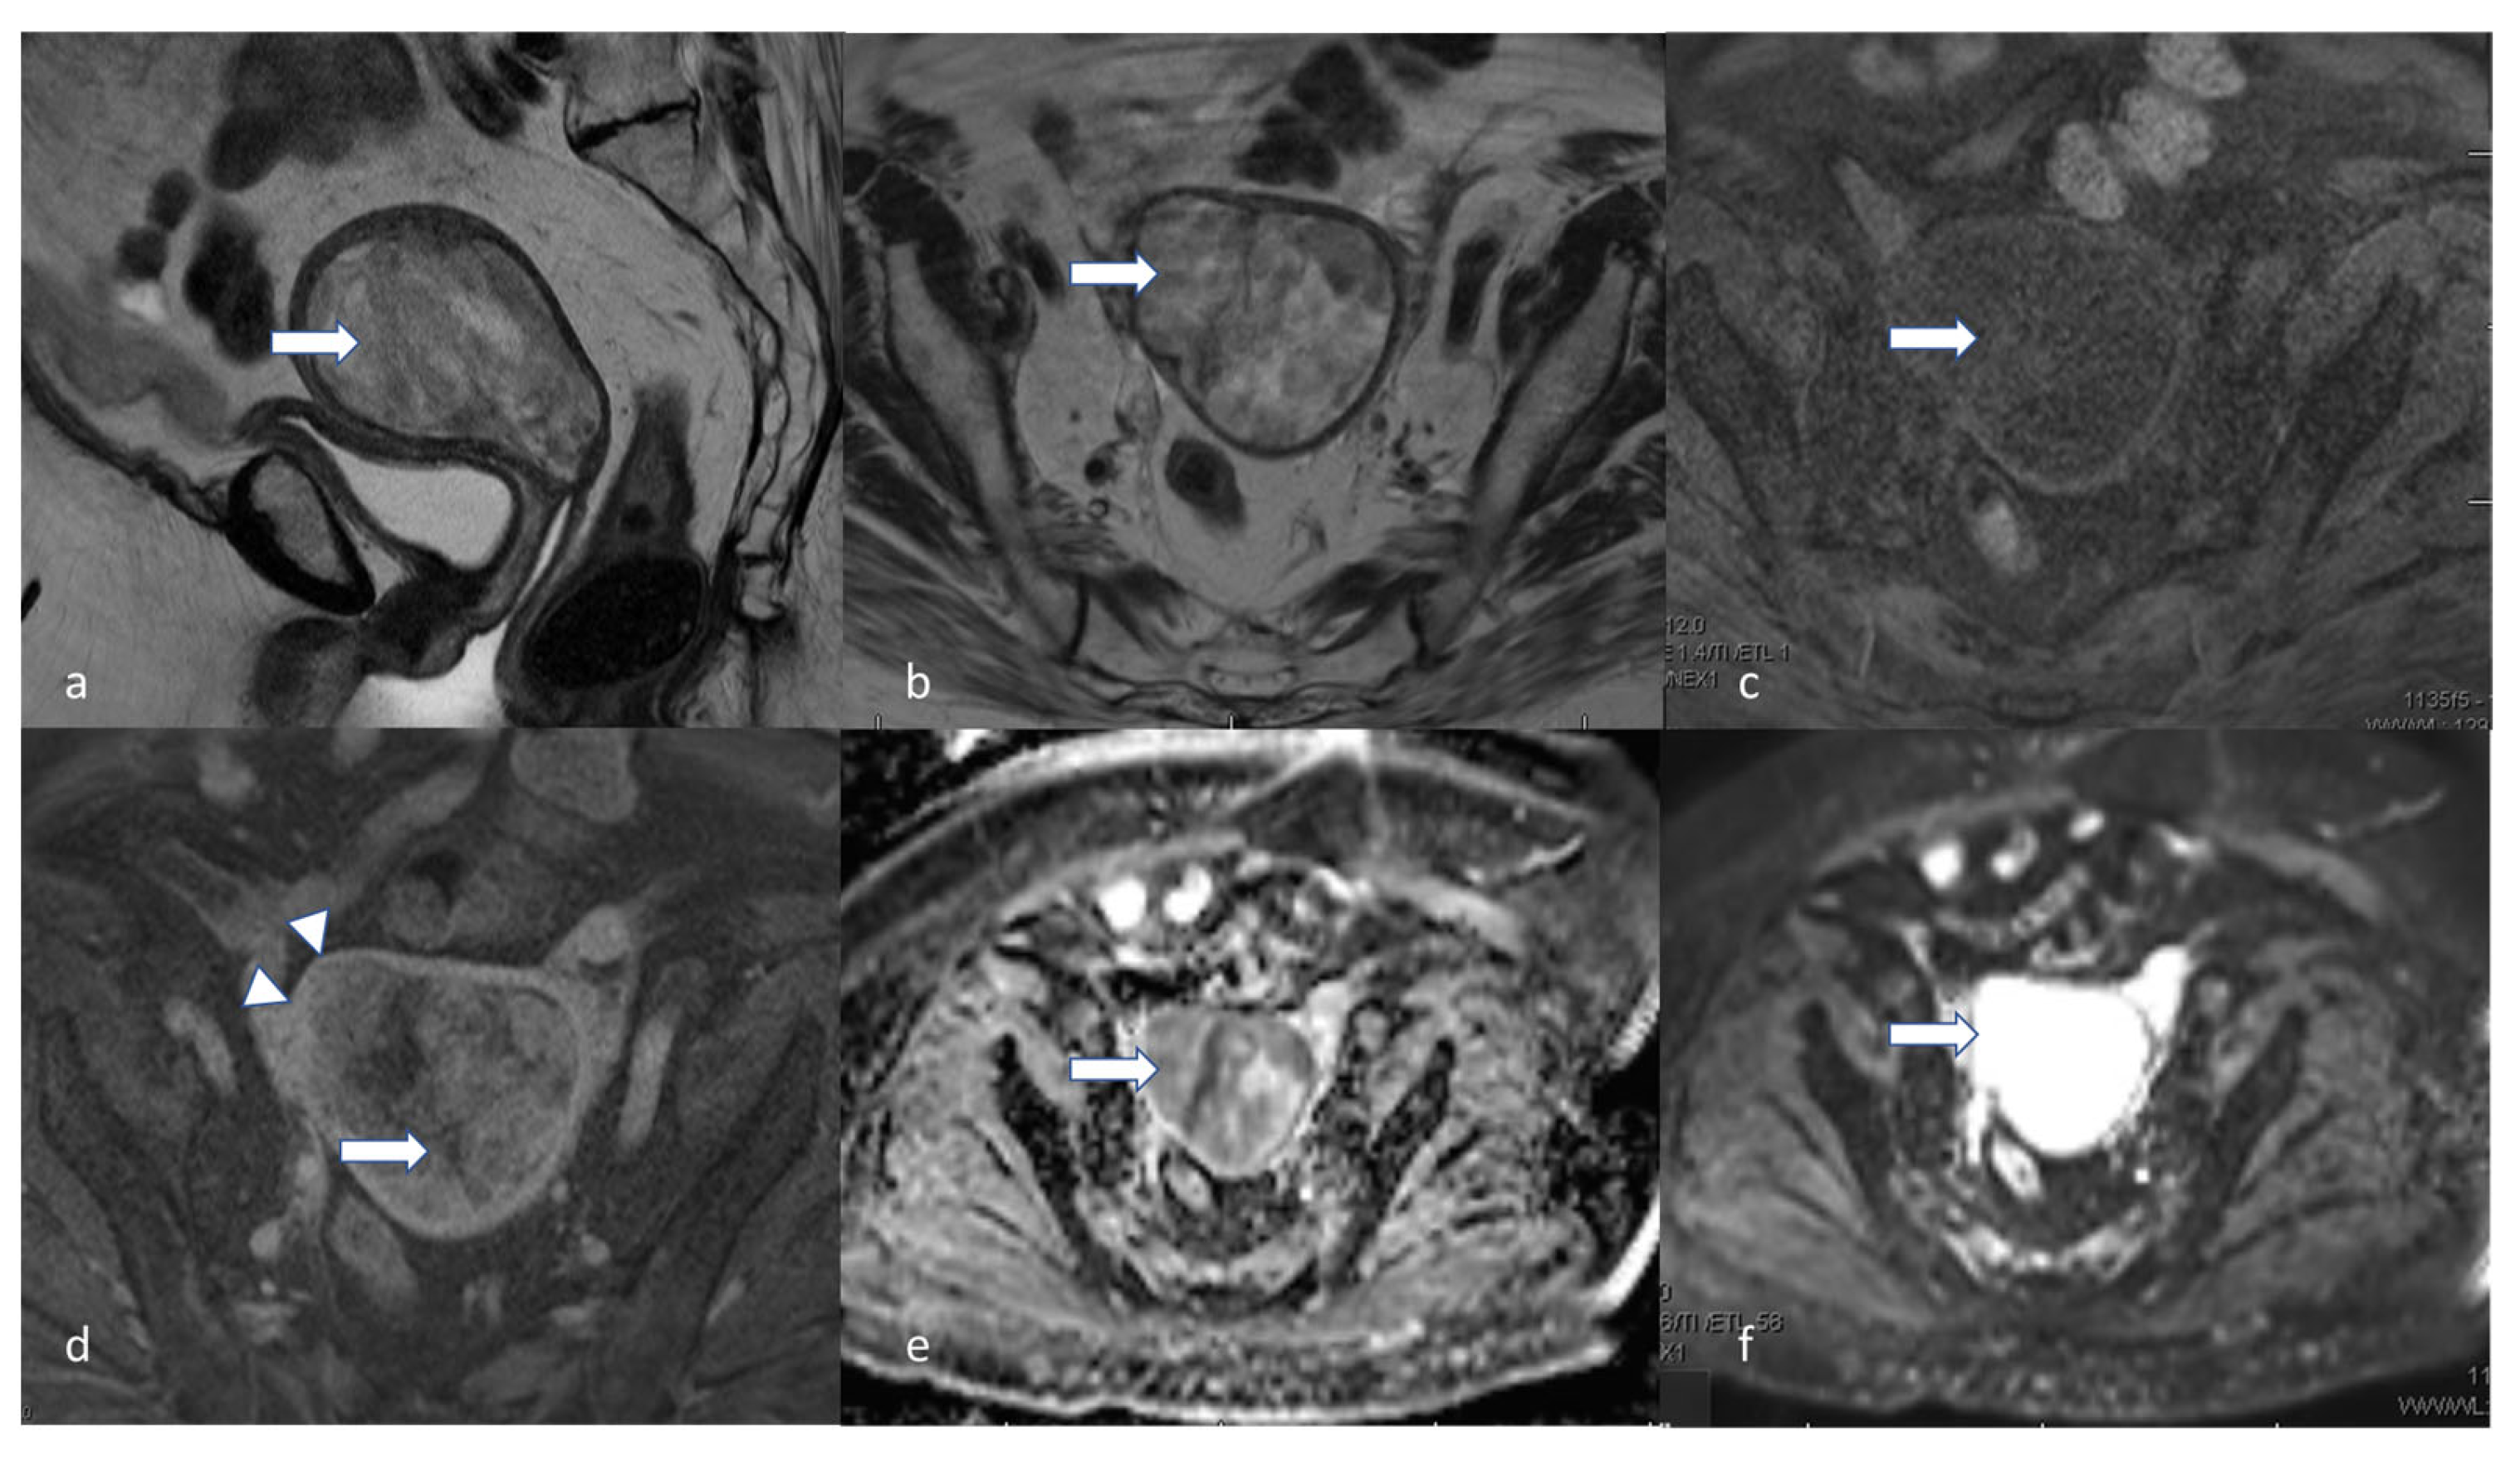

5.3. Magnetic Resonance Imaging (MRI)

- Maheshwari, E.; Nougaret, S.; Stein, E.B.; Rauch, G.M.; Hwang, K.-P.; Stafford, R.J.; Klopp, A.H.; Soliman, P.T.; Maturen, K.E.; Rockall, A.G.; et al. Update on MRI in Evaluation and Treatment of Endometrial Cancer. RadioGraphics 2022, 42, 2112–2130. [Google Scholar] [CrossRef] [PubMed]

- Xu, G.; Wang, D.; Ling, X.; Lu, H.; Lin, R.; Shi, Y.; Zhang, B. Diagnostic Value of Assessment of Cervical Involvement in Early-Stage Endometrial Adenocarcinoma: Comparison of Magnetic Resonance Imaging (MRI) Versus Hysteroscopy. Med. Sci. Monit. 2018, 24, 7952–7957. [Google Scholar] [CrossRef] [PubMed]

- Bi, Q.; Bi, G.; Wang, J.; Zhang, J.; Li, H.; Gong, X.; Ren, L.; Wu, K. Diagnostic Accuracy of MRI for Detecting Cervical Invasion in Patients with Endometrial Carcinoma: A Meta-Analysis. J. Cancer 2021, 12, 754–764. [Google Scholar] [CrossRef]

- Nougaret, S.; Horta, M.; Sala, E.; Lakhman, Y.; Thomassin-Naggara, I.; Kido, A.; Masselli, G.; Bharwani, N.; Sadowski, E.; Ertmer, A.; et al. Endometrial Cancer MRI staging: Updated Guidelines of the European Society of Urogenital Radiology. Eur. Radiol. 2019, 29, 792–805. [Google Scholar] [CrossRef]